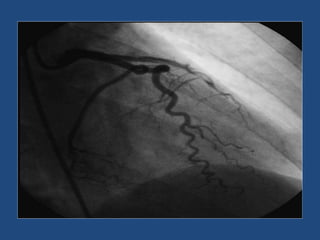

5 semanas después

A los 2 meses